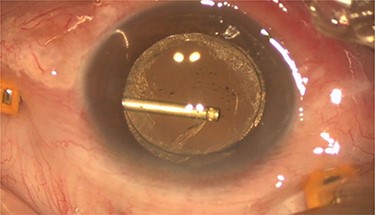

On examination, both eyes showed a quiet conjunctiva with clear corneas and quiet pseudophakia. Anterior chamber was deep and equal in both eyes. Left eye showed dense turbid fluid behind the IOL, with multiple pitting on the IOL, indicating a previous trial of Nd:YAG capsulotomy (Fig. 1). Posterior capsule could not be visualized by the slit lamp. Right eye showed a clear capsular bag with a good view of the fundus. Fundus exam showed mild non-proliferative diabetic retinopathy and dry macula in the right eye and no view of the fundus in the left eye.

Pre-operative slit lamp photo showed turbid fluid behind the IOL, and the IOL pitting indicates a previous trial of YAG capsulotomy.